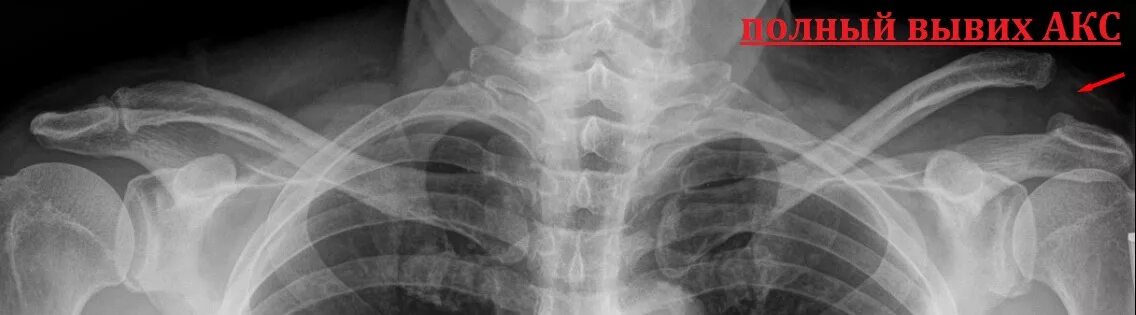

Вывих акромиально ключичного сочленения